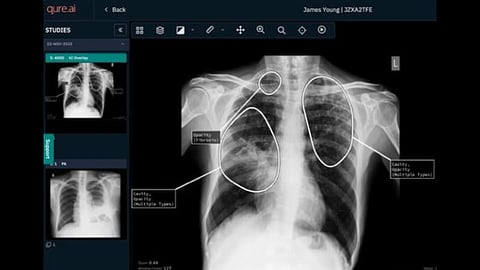

Global digital health company Qure.ai has received an $8 million grant from the Gates Foundation to advance AI-powered diagnostics for preventable infectious diseases, including tuberculosis (TB) and pneumonia. The funding aims to strengthen health equity by improving access to early, high-quality diagnostics in under-resourced regions.

The project builds on Qure.ai’s decade-long experience deploying AI-powered diagnostic tools in challenging environments, including remote regions of sub-Saharan Africa, rural Southeast Asia, and high-altitude settings. Its AI-enabled chest X-ray solutions have demonstrated the ability to significantly reduce diagnostic turnaround times for TB from weeks to just one to two days, even in settings without on-site clinicians.